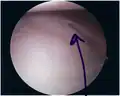

Bankart lesion seen at arthroscopy Bankart lesion seen at arthroscopy